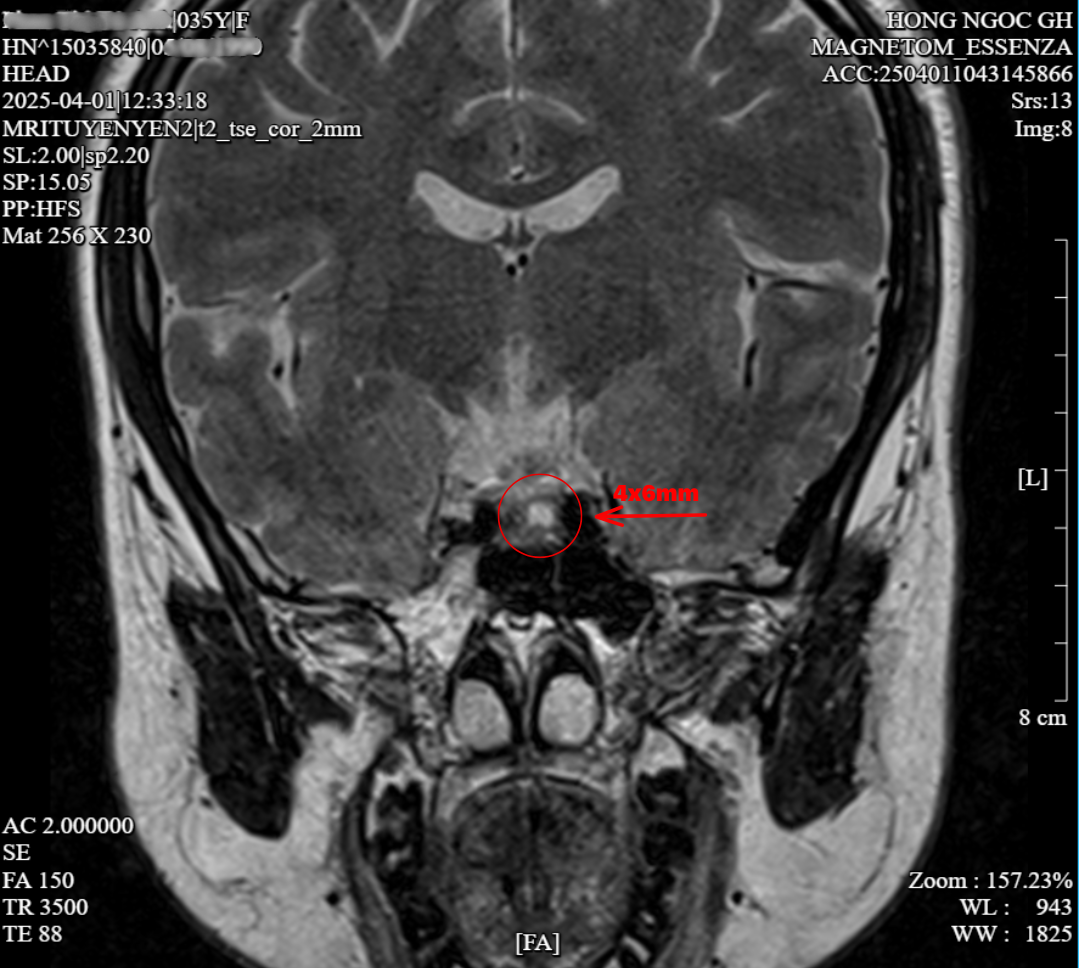

Tuy nhiên, để điều trị triệt để, bác sĩ cần chẩn đoán chính xác căn nguyên gây ra bệnh. Bệnh nhân P.T.T được chỉ định chụp MRI, phát hiện có tổn thương nhỏ kích thước 4x6mm thùy sau tuyến yên lệch trái - nghi ngờ là nguyên nhân tăng tiết ACTH - dẫn đến tăng sản xuất Cortisol.

Tổn thương kích thước 4x6mm ở thùy sau tuyến yên lệch trái